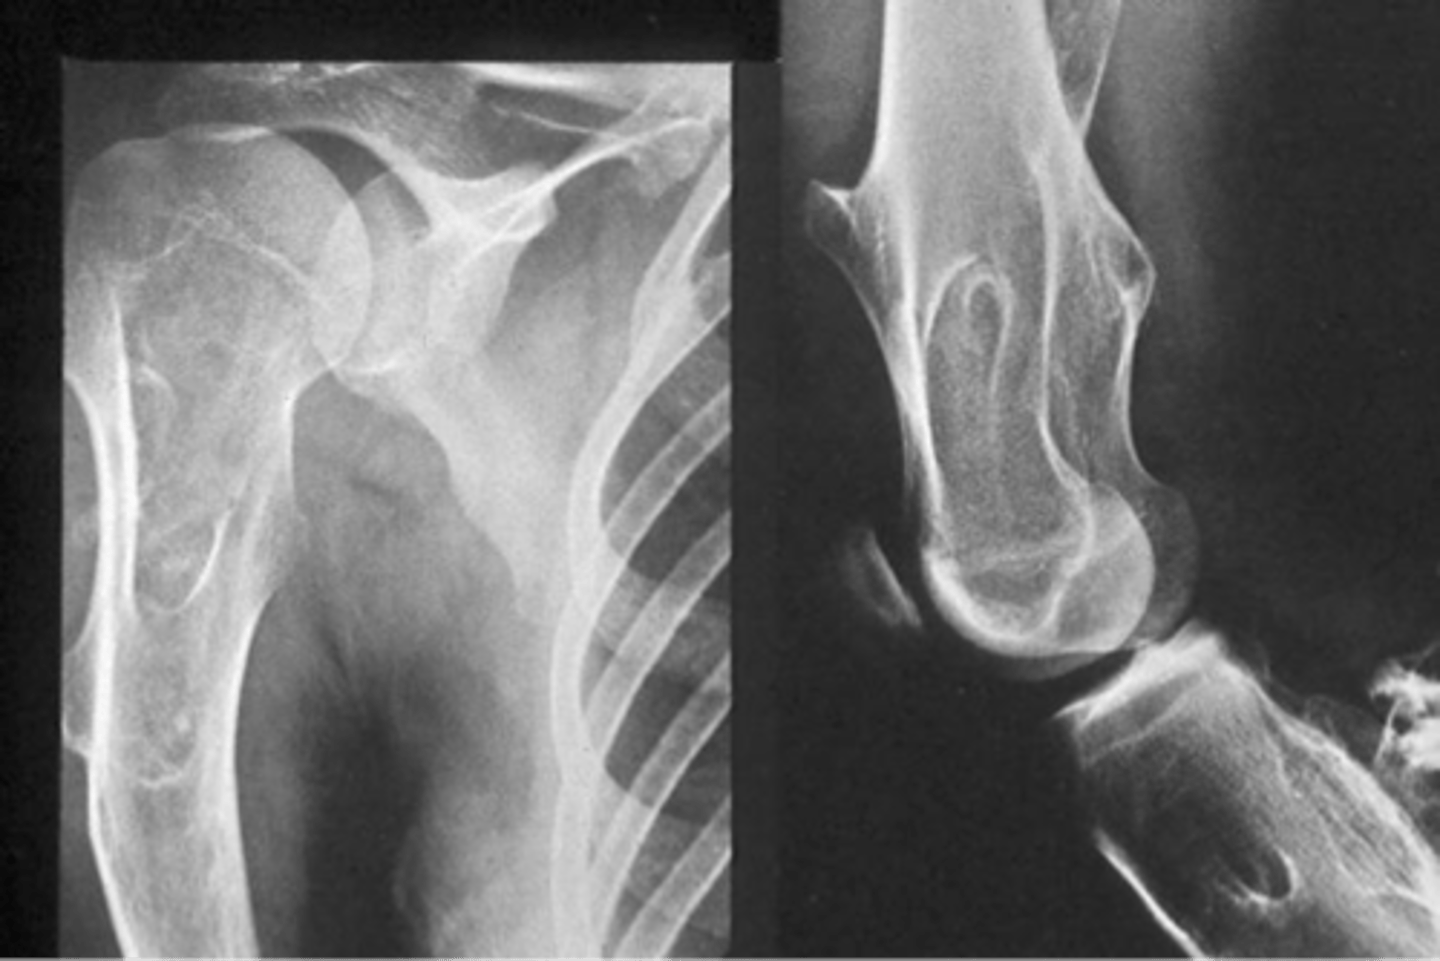

Hereditary multiple exostoses

- Inherited metaphyseal overgrowth

- Multiple painless osteochondromas

- Identical to solitary

- Discovered 2-10 y.o.

- Knee, ankle, shoulder, wrist

5-25%

Hereditary multiple exostoses malignant transformation rate